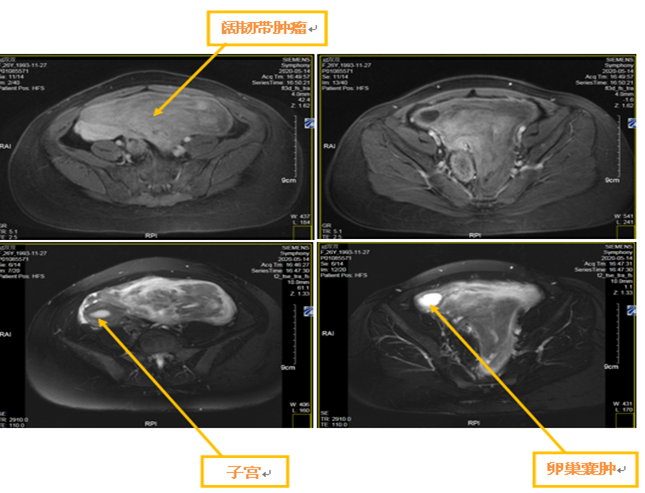

闻强医生处理过无数子宫肌瘤,但当他看见这名患者的盆腔磁共振时,还是吃了一惊。只见她的盆腔被一个巨大的不规则实性肿块占据,子宫被挤到了一边,明显偏离了中线位置。肿块形状奇怪,有点像“蘑菇”,蘑菇柄一直向下突出到子宫直肠窝,位置非常低。不仅如此,在子宫和肿块之间似乎还有一个卵巢囊肿。

此时,闻强心中有了点底,这很有可能是一个子宫阔韧带肌瘤。肿块和子宫的分界还是比较清楚的,保住子宫应该问题不大,但是左侧输尿管和髂血管正好从肿块下方通过,能否将其成功分离,避免损伤,还是个未知数。另外,这么大的肌瘤往往血供丰富,术中如何避免大出血?还有,肿块距离直肠也比较近,万一伤到直肠怎么办?

5月26日,手术开始,空气里弥漫着紧张的气氛。术中探查所见:和术前设想的一致,是一个子宫阔韧带肌瘤,合并左卵巢囊肿。为了不影响子宫肌瘤的手术,首先行左卵巢囊肿剔除+左卵巢成形术。然后分离阔韧带肌瘤和左输尿管以及髂血管等周围组织的粘连,虽然肿块与上述组织之间粘连致密,但仍然顺利将其游离。